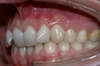

Vues avant le traitement